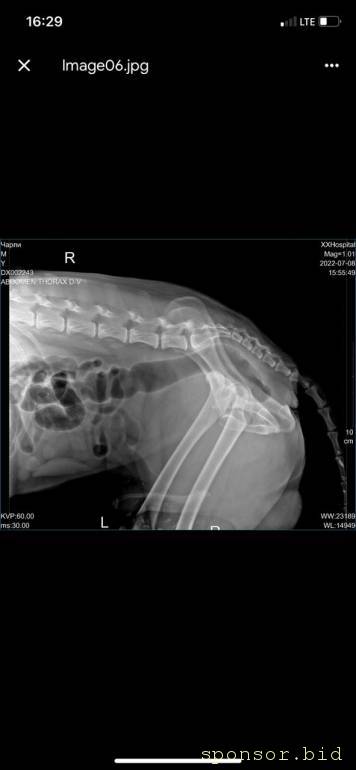

рентген

Помощь сбитой собачке - рентген 6.jpeg

Помощь сбитой собачке - рентген 1.jpeg

Помощь сбитой собачке - рентген 2.jpeg

Помощь сбитой собачке - рентген 3.jpeg

Помощь сбитой собачке - рентген 4.jpeg

Помощь сбитой собачке - рентген 5.jpeg

08.07.2022 г. передо мной на Варшавском шоссе сбили собаку, человек совершивший наезд даже не остановился и укатил дальше, я выбежала из машины, смогла остановить движение пары соседних полос, чтобы пес мог отползти на траву ( поднять и перенести не представлялось возможным, т.к. мне нельзя поднимать более 2 кг, более того непонятно что могла сделать собака в состоянии стресса и шока), после чего нашла парковку для машины и побежала к собаке, благо на тот момент несколько неравнодушных людей уже окружили его (это мальчик). Нами была вызвана полиция, составлено заявление ( но, думаем вряд ли кто-то будет этим заниматься.. так же сделан запрос в московскую службу видеофиксации, чтобы был сделан архив видео, если там есть камеры (тогда было не до этого, чтобы рассматривать есть ли они там), и в последствии приобщить к делу, или хотя бы найти того козла). Договорились со службой отлова, чтобы они на своей газели помогли довезти собаку до клиники шанс био, т.к. непонятно было что у нее с лапами, в клинике сделали рентген, несколько капельниц, обработали рану (т.к. задняя лапа разодрана до кости), взяли анализы, вкололи обезболивающие и отпустили.. т.к. у них нет стационара для бездомных, а так же хирурга, который мог бы сделать операцию. по заключению - кровоизлияние в глаз, открытая рана на левой заплюсне, вывих левого тбс (но вправить его нельзя, нужно делать операцию) порваны связки. по сумме в клинике оставили 14 500 руб. далее собаку отвезли в стационар надежда, с пятницы по воскресенье - обошлось в 10 552 руб (сам стационар, плюс лекарства, уколы и обработка ран, консервы, но он не ел). сегодня собаку возили на консультацию к хирургу в клинику беланта, было сделано дополнительно узи, на данный момент необходимо стабилизировать собаку, т.к. она еще в состоянии шока и с пятницы даже не ела, сейчас его опять повезли в стационар, необходимо еще делать уколы и обрабатывать рану, так же необходимо сделать 2 операции: на бедро (27200) и колено(55000), чтобы он смог передвигаться. в клинике заплатили 8167 с учетом лекарств. завтра планируется прием е еще одному хирургу в добрые руки, там по телефону озвучили цены на операции ниже чем в беланте, но нужен осмотр хирурга и его заключение. итого на данный момент на собачку ушло 33 219 руб. просим в сложившейся ситуации финансово помочь в судьбе пса, возможно найти ему любящих хозяев, на улицу его выкинуть уже просто невозможно, он там погибнет.. пес безумно умный, терпеливый, добрый, за все время ни разу не пытался агрессировать, укусить или что-то еще..